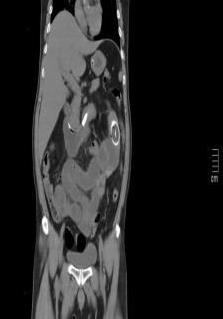

• 超声内镜引导下胃旁曲张静脉精准断流术治疗食管胃静脉曲张出血的疗效分析(附20例报告)

2025, 31(8):85-90. DOI: 10.12235/E20250036

摘要 (153) HTML (42) PDF 5.38 M (98) 评论 (0) 收藏

摘要:目的 探讨超声内镜引导下胃旁曲张静脉精准断流术治疗食管胃静脉曲张出血的疗效。方法 回顾性分析2024年1月1日-2024年12月31日于该院接受超声内镜引导下胃旁曲张静脉精准断流术治疗的20例肝硬化食管胃静脉曲张出血患者的临床资料,并评估治疗效果。结果 20例患者均顺利完成超声内镜引导下胃旁曲张静脉精准断流术;注射组织胶联合置入弹簧圈(16例)和单独注射组织胶(4例)均成功阻断胃旁来源的曲张静脉;所有患者均未发生穿孔、食管贲门狭窄、大出血、败血症和异位栓塞。1例单独注射组织胶的患者,术后胃旁曲张静脉少许渗血,经降低门静脉压力治疗3 d后好转,另1例单独注射组织胶患者,术后出现低热,抗感染3 d后体温恢复正常。结论 超声内镜引导下胃旁曲张静脉精准断流术治疗食管胃静脉曲张出血的临床疗效好,异位栓塞、大出血、感染和穿孔等并发症少,但仍需要密切随访,观察胃旁曲张静脉的排胶问题。